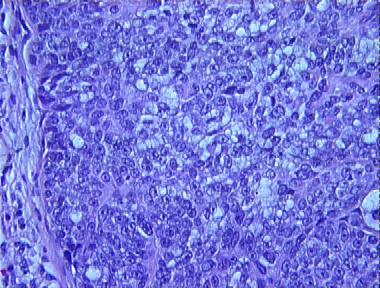

basal cell carcinoma with sebaceous differentiation

Histologic Features